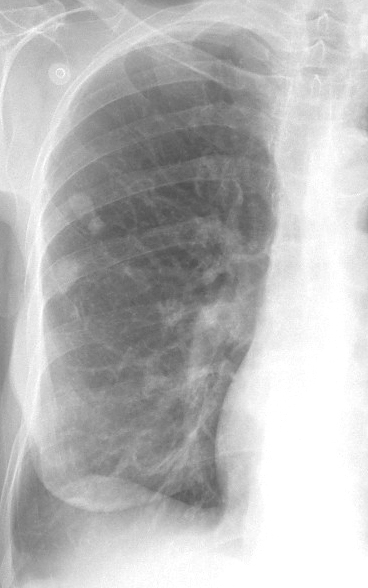

Gallery COPD muc plugs

muc plugs